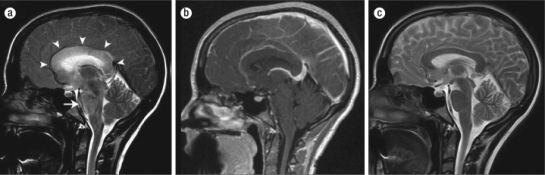

Les imatges mostren la hipertensió anormal que pateix el cervel pel consum deThermatrim / Baylor University Medical Center Proceedings